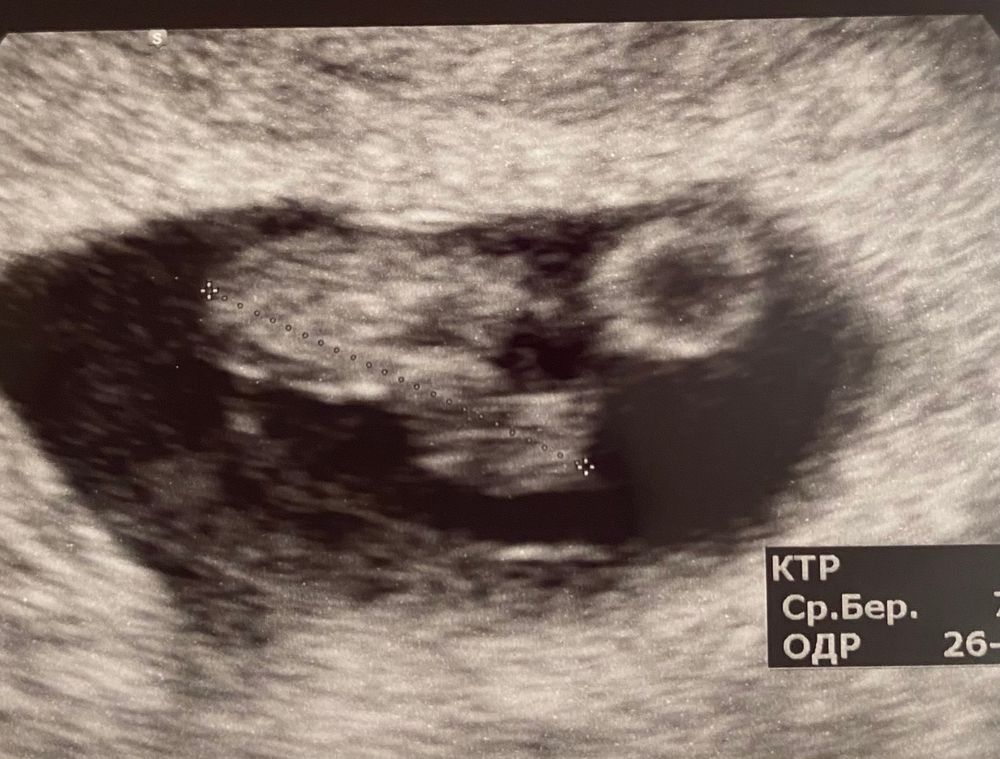

Результат 8 недели узи

Ну вот дошли мы до 8 недель) сколько было переживаний за это время не передать. Две недели назад была кровь поехала сразу на узи, сказали гематома и сюрприз 2 эмбриона 😁 правда у второго пока нет сб. Я вышла в шоке наша девочка поделилась. Сказали переделать узи через неделю, прошла неделя этот же узист уже не видит второй эмбрион 🤷♀️ но размер ктр очень маленький для нашего срока и шейку ставит мне 27 мм а была 36 мм. Я вышла в шоке, мне посоветовали хорошего врача вчера была у нее и все замечательно ктр соответствует своему сроку шейка 36 мм и да 2 эмбрион есть но он замер( Но я очень рада что с нашей второй крошкой все хорошо растем💪